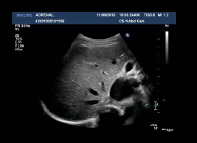

what plane is this?

trans. the below is long